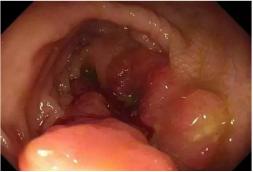

女性,75岁,因“排便次数增多2月余”入院。患者2月前无明显诱因出现排便次数增多,每日排便20余次,多为黏液便。后于外院查全腹部CT示:乙状结肠肠壁增厚,周围可见少量气体影;肠镜示结肠肿瘤(见图1-1),病理提示高度疑癌。体格检查示左下腹可及直径约10cm肿物,压痛(+),未及反跳痛。辅助检查:白细胞13.44×109/L ,超敏C反应蛋白 39.08mg/L,血红蛋白91g/L,白蛋白33.2g/L,血钾2.42mmol/L。以乙状结肠肿瘤伴穿孔入院。入院后予以禁食、肠外营养支持、抗感染等治疗一周后行剖腹探查术,术中探查发现盆腔可见黄色积液300ml、肿瘤近端肠壁可见撕裂样穿孔,局部有脓胎覆盖,近端肠管水肿明显,遂行左半结肠切除+横结肠造口术+腹腔引流术,术程顺利。术后恢复顺利,10天后出院。

图1-1肠镜见结肠肿瘤